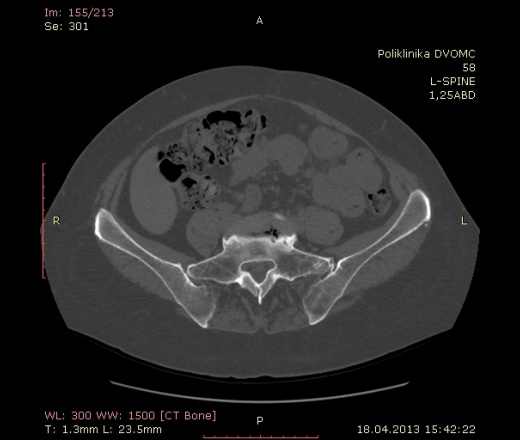

имхо: эностоз. Но, своё слово должны сказать специалисты по КТ.

Тоже предполагаю эностоз.

Можно ли в этом случае рекомендовать КТ в динамике через 6 месяцев? Или все-таки на дообследование на МРТ лучше направить? В буржуйской ли-ре сказано, что МРТ способна отличить эностоз от mts.

А КТ не может?

"В некоторых случаях их(эностозы) бывает трудно отличить при КТ от остеобластических метастазов, однако они не усиливаются при МРТ с внутривенным контрастированием...." "В то время как при КТ лучше выявляются поражения компактной костной ткани, МРТ имеет преимущества в диагностике метастазов в губчатое вещество...."

Так пишет господин Прокоп вместе с товарищем Галански в книжке своей.

скорее всего островок компактного вещества

специфичность кт низка при одиночных поражениях,мрт T1,T2-гипоинтенсивный сигнал,подавление жира-изо или гиперинтенсивный сигнал,путаница на мрт в следующем-оба процесса дают отек кости и здесь возникают трудности,но размер менее 3 см и типичные показатели являются показателями доброкачественности,самый показательный и точный метод -сцинтиграфия при которой медуллярная остеома не обнаруживает накопления,мтс четко накапливает

Спасибо. Вообщем будем считать что эностоз.